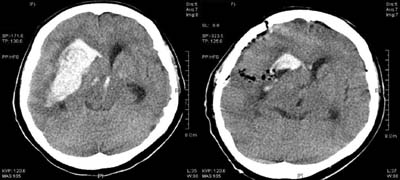

<ÇãÇ÷¼º

³úÁ¹Áß>

ÁÂÃø

Áß³úµ¿¸ÆÀÇ Æó»öÀ¸·Î ÀÎÇÑ ³ú°æ»ö¼Ò°ß(Ç÷°üÁ¶¿µ¼ú»ó

Áß³úµ¿¸ÆÀÌ º¸ÀÌÁö ¾Ê°í ÀÖ´Ù)

<°íÇ÷¾Ð¼º

³úÃâÇ÷>

<¼ö¼ú

Àü> <¼ö¼ú

ÈÄ>

¿ìÃø

Çǰ¢ºÎ ÃâÇ÷ȯÀÚÀÇ ³úCT¼Ò°ß(¼ö¼úÈÄ Ç÷Á¾ÀÌ

Á¦°ÅµÇ¾îÀÖ´Ù)